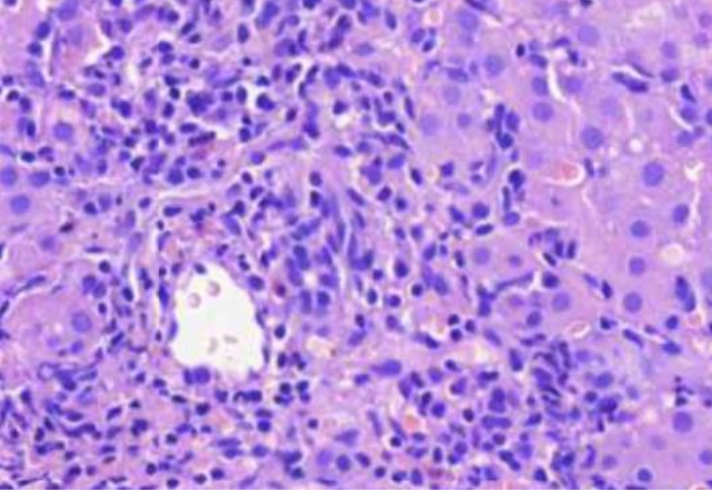

Kirkassoluinen munuaiskarsinooma

MIKÄ TAUTI? Kasvaimen vaskulaari-invaasiota perirenaalisessa rasvakudoksessa.